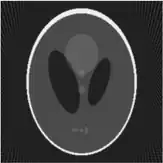

If a function represents an unknown density, then the Radon transform represents the projection data obtained as the output of a tomographic scan. Hence the inverse of the Radon transform can be used to reconstruct the original density from the projection data, and thus it forms the mathematical underpinning for tomographic reconstruction, also known as iterative reconstruction.

The process of reconstruction produces the image (or function in the previous section) from its projection data. Reconstruction is an inverse problem.

Thus in an image processing context the original image can be recovered from the 'sinogram' data by applying a ramp filter (in the variable) and then back-projecting. As the filtering step can be performed efficiently (for example using digital signal processing techniques) and the back projection step is simply an accumulation of values in the pixels of the image, this results in a highly efficient, and hence widely used, algorithm. Explicitly, the inversion formula obtained by the latter method is:[4]